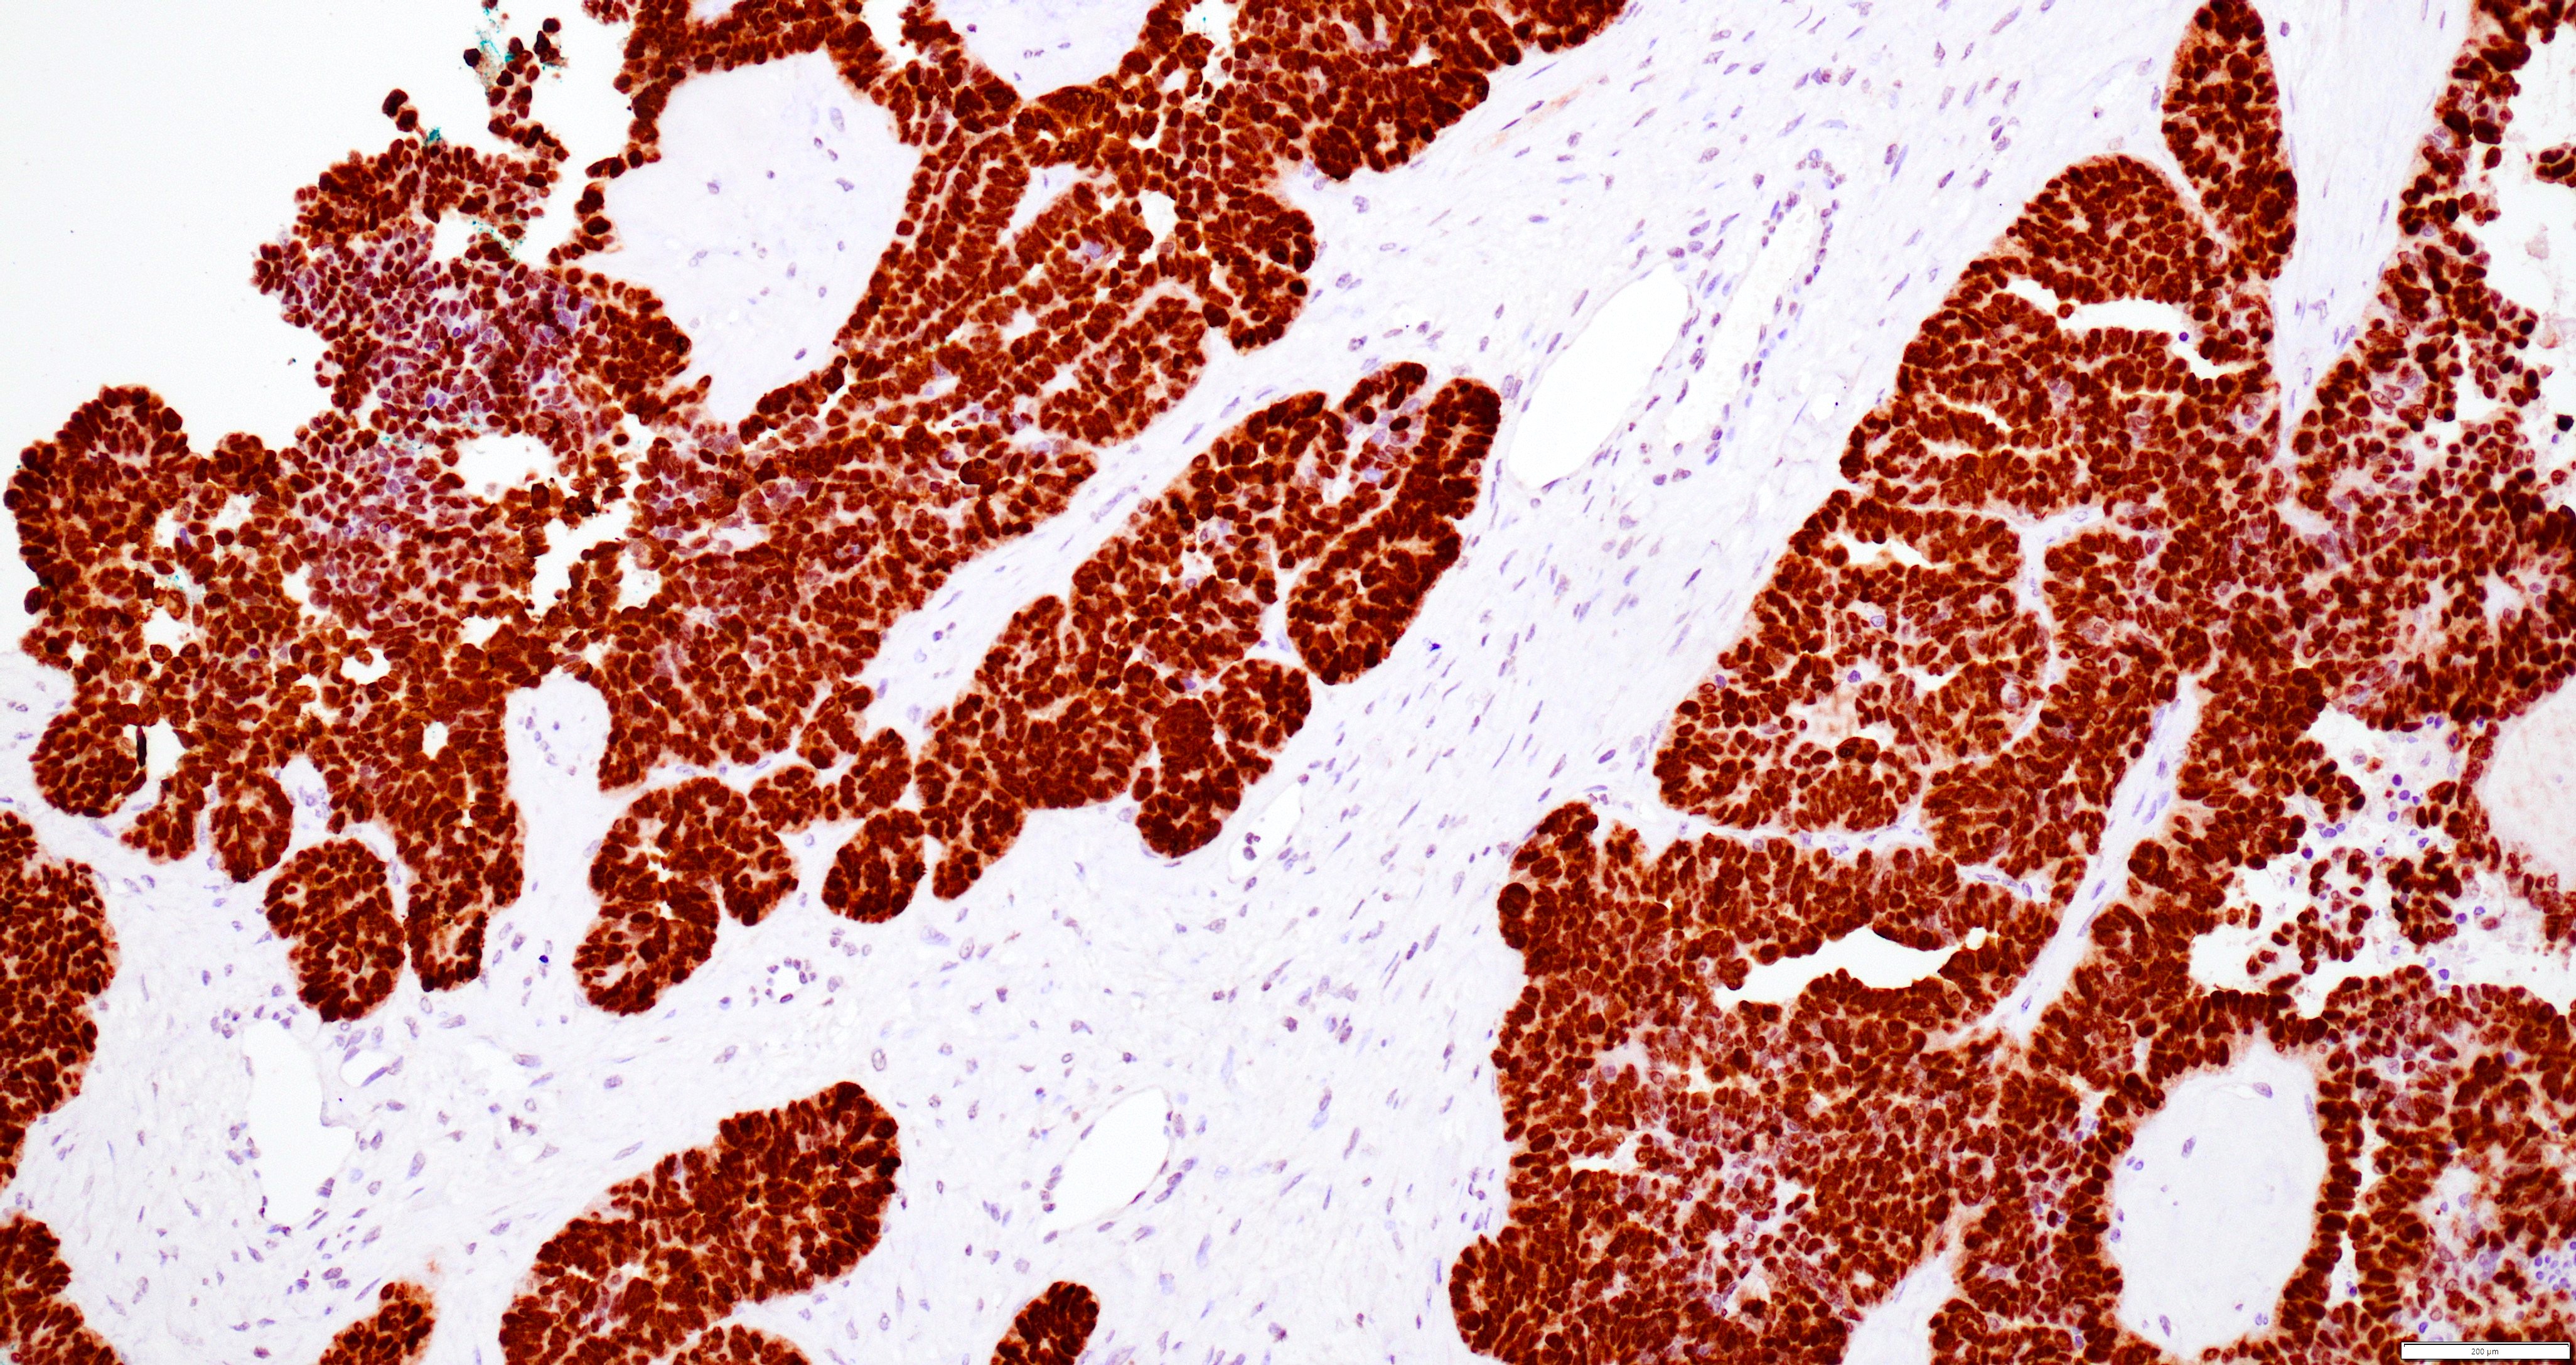

Microscopic (histologic) images

Contributed by Daniel Graham, M.D., Adele Wong, M.B., B.Ch., B.A.O. and Lucy Ma, M.D.

Positive stains

- PAX8: usually diffusely positive

- GATA3 and TTF1: focal or diffuse with inverse staining pattern described in several studies in the most recent WHO classification; cells positive for GATA3 are negative for TTF1 and vice versa (Am J Surg Pathol 2018;42:1596)

- CD10: focal and apical / luminal

- p53 wild type

- MMR proficient